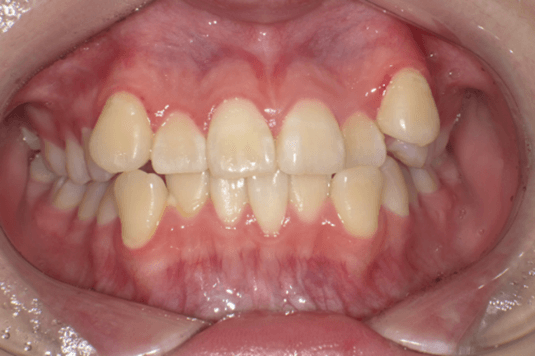

13歳8か月の女子(初診時:写真a)

主訴は左上に八重歯がある。右側Angle ClassII 左側Angle Class I、FMA 36.6°、A.L.D.(凸凹の量/上顎 -10.0mm、下顎 -4.0mm)